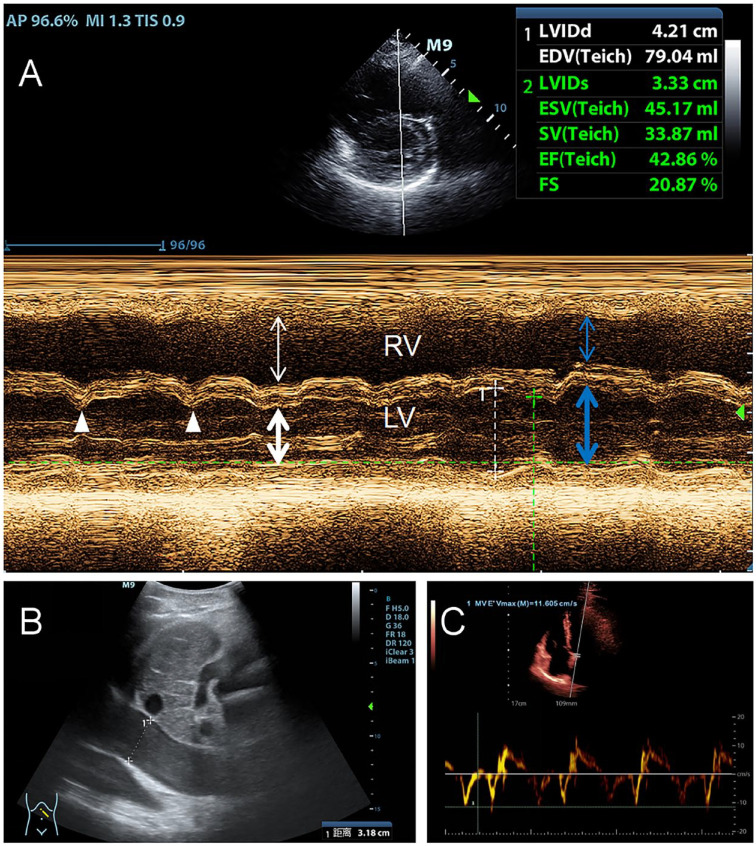

由于心包炎症和纤维化,缩窄性心包炎可导致舒张期心室充盈受损。收缩性心包炎的诊断需要通过超声心动图确定结构和血流动力学特征。我们报告了一例缩窄性心包炎病例,其表现形式为呼吸困难和下肢水肿在 7 年时间里逐渐加重。患者通过超声心动图确诊为缩窄性心包炎,并接受了心包切除术。

Constrictive pericarditis can lead to compromised diastolic ventricular filling due to pericardial inflammation and fibrosis. A diagnosis of constrictive pericarditis was established by identifying structural and hemodynamic features through echocardiography. We present a case of constrictive pericarditis, which manifested in the form of gradually worsening dyspnea and lower-extremity edema over a 7 years period. The patient was diagnosed with constrictive pericarditis using echocardiography, and underwent a pericardiectomy.